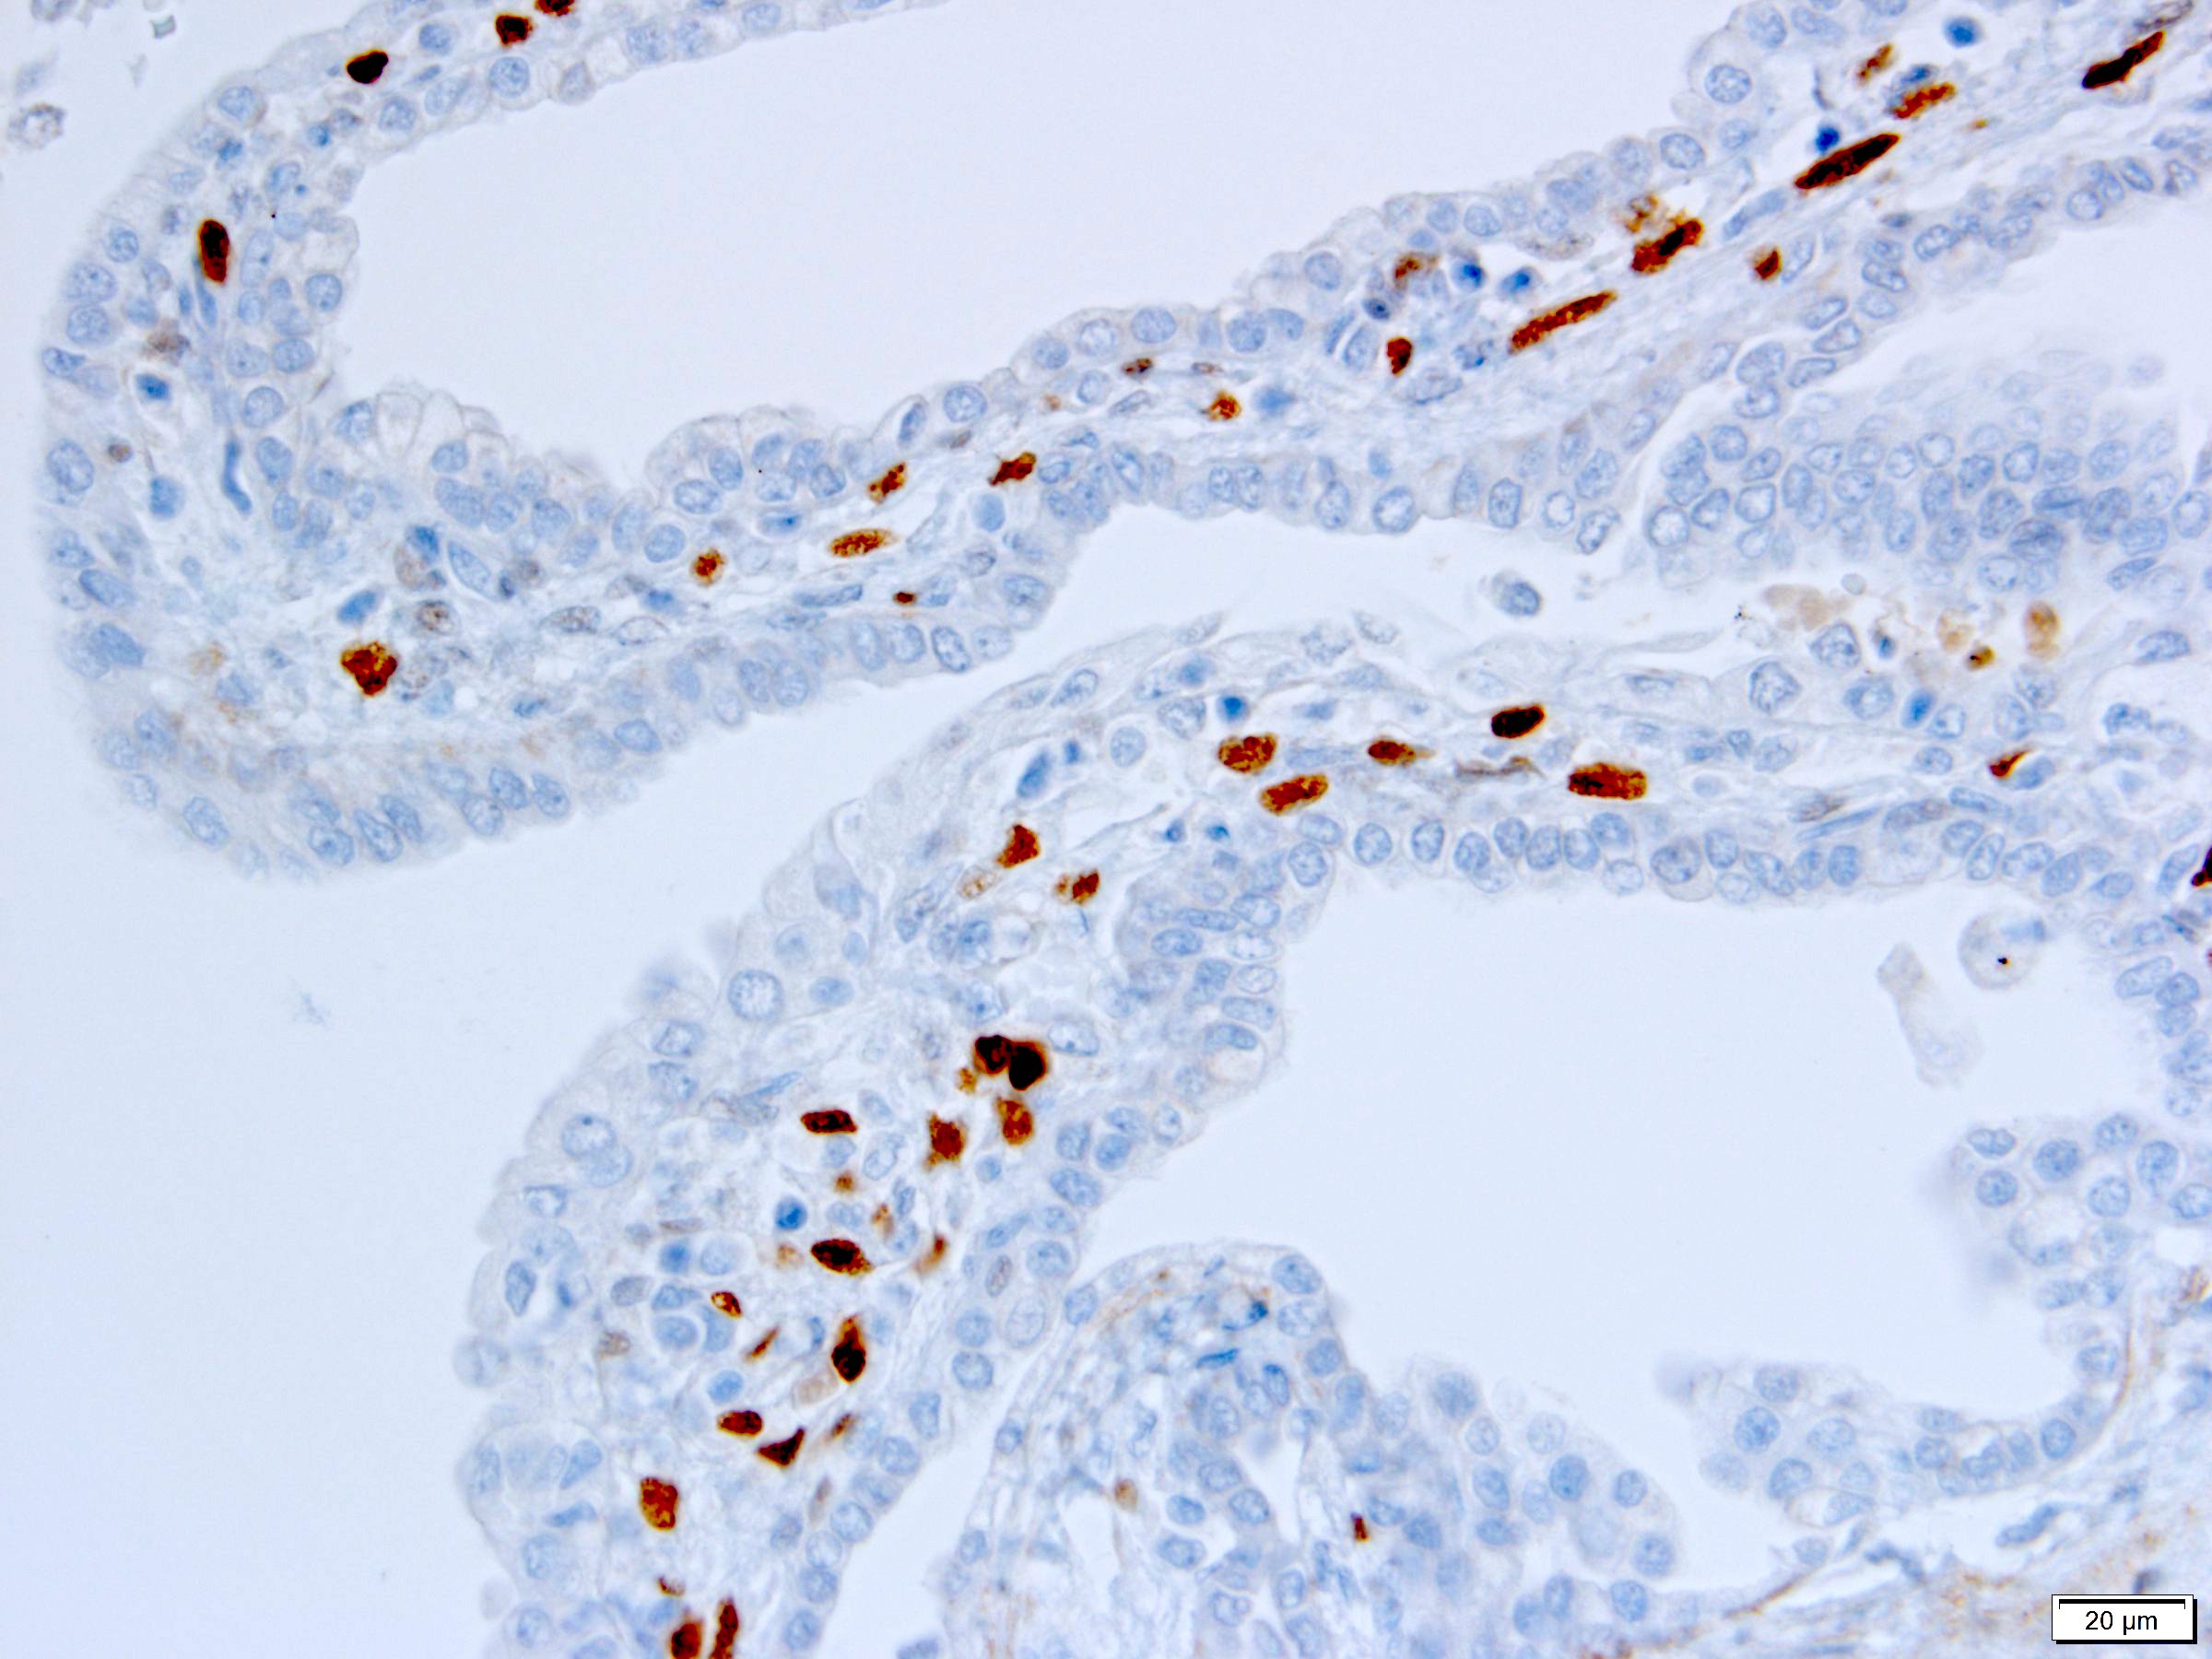

Positive stains

- Stroma:

- SMA: strong and diffuse, 95% (Am J Surg Pathol 2016;40:1591, Arch Pathol Lab Med 2004;128:1404, Arch Pathol Lab Med 2006;130:80)

- Desmin and caldesmon: more variable, 42% and 60%, respectively (Am J Surg Pathol 2016;40:1591, Arch Pathol Lab Med 2004;128:1404)

- ER and PR, 50% and 95%, respectively (Am J Surg Pathol 2016;40:1591, Arch Pathol Lab Med 2004;128:1404, Arch Pathol Lab Med 2006;130:80, Am J Surg Pathol 2007;31:489)

- CD10: mainly in spindle cells around epithelial elements, 81% (Am J Surg Pathol 2016;40:1591, Arch Pathol Lab Med 2004;128:1404, Am J Surg Pathol 2007;31:489)

- FOXL2: in ovarian type stroma, 90% (Hum Pathol 2014;45:1010)

- Comment: The sections show a well circumscribed tumor composed of multiple cysts lined by flattened or cuboidal epithelium. Immunohistochemistry was performed to show the septal stroma is positive for ER and PR. The morphologic and immunohistochemical findings support the diagnosis of adult cystic nephroma.

A 6 cm predominantly well circumscribed, multicystic mass was incidentally found in a 55 year old woman. Sections of the partial nephrectomy showed the above histologic features. The stromal component is positive for ER and PR (shown above). What is the likely diagnosis?

A. Adult cystic nephroma. Adult cystic nephroma is a well circumscribed, predominantly cystic mass. Angiomyolipoma with epithelial cysts shares overlapping histologic features but the stroma is immunopositive for melanocytic markers. Cystic partially differentiated nephroblastoma typically occurs in children. Multilocular cystic neoplasm of low malignant potential has nests of tumor cells with abundant clear cytoplasm and small nuclei without prominent nucleoli. None of the above choices, except for adult cystic nephroma, demonstrate immunoreactivity for ER and PR.